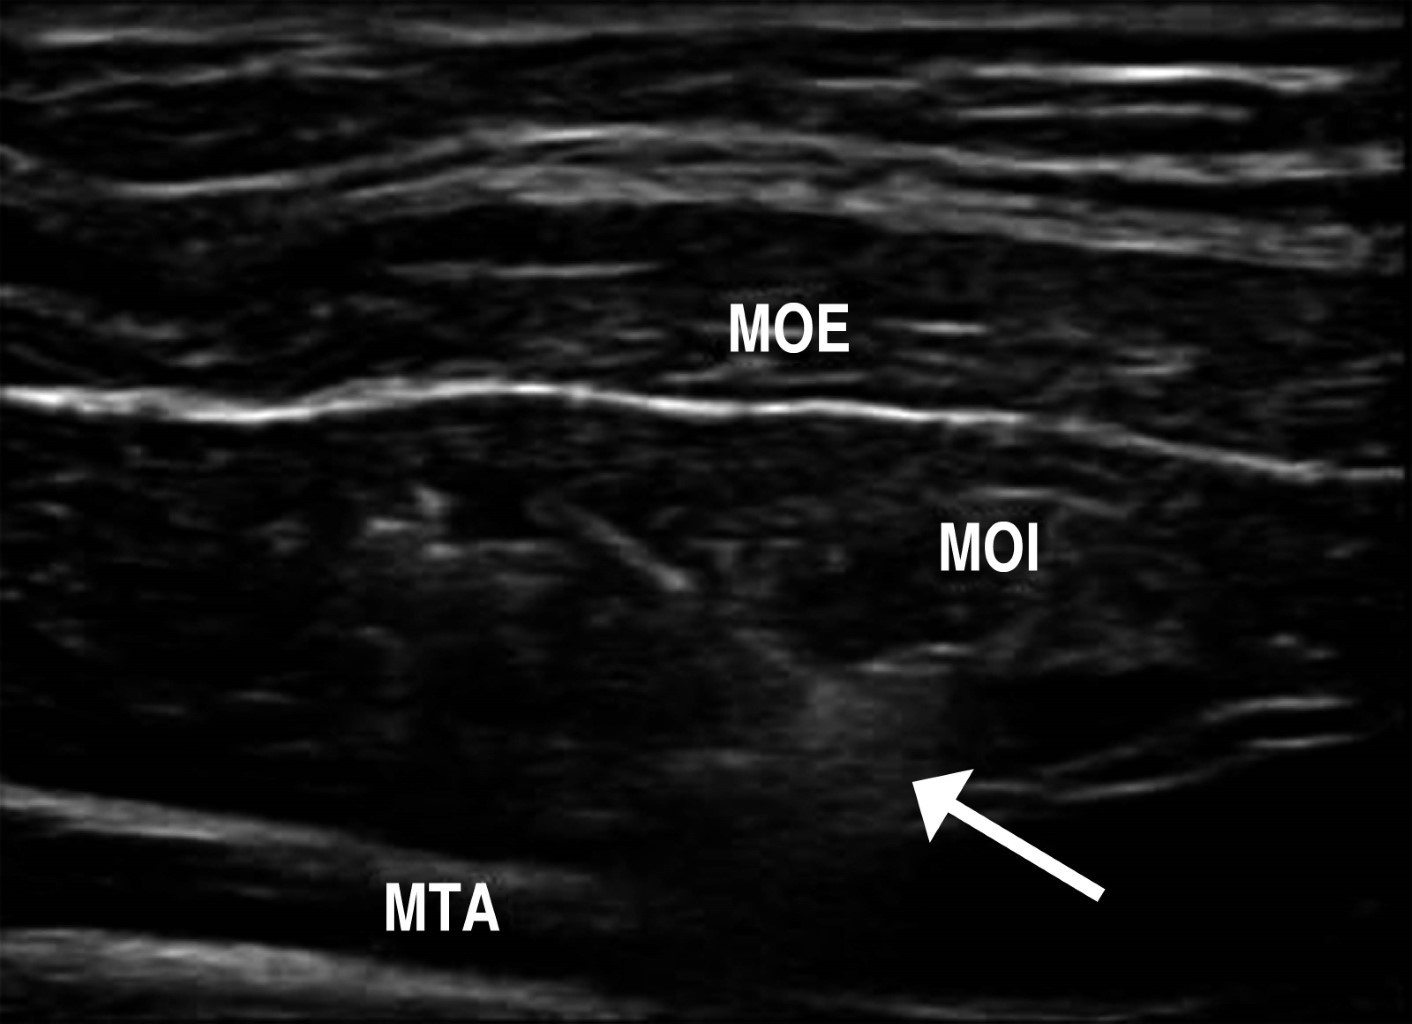

Con ayuda de equipos de ultrasonido portátiles es factible realizar en quirófano bloqueos anestésicos que contribuyen a disminuir el dolor posoperatorio y permitir incluso algunos procedimientos como las plastías inguinales abiertas bajo anestesia local y sedación, las plastías de hernias umbilicales y de la línea media. El bloqueo del plano del transverso abdominal30 se emplea colocando el transductor en el flanco en un plano axial, en el punto medio de la distancia entre la cresta iliaca y el borde costal inferior. Se identifica con el transductor la imagen de los músculos del componente lateral y, empleando una dilución de bupivacaína o ropivacaína, se introduce la aguja bajo guía sonográfica hasta que se identifica la penetración de los dos músculos oblicuos y se infiltra justo entre el oblicuo interno y el músculo transverso abdominales (Figura 8). Este procedimiento produce un bloqueo que puede abarcar desde los dermatomas T9 al L1. Su principal utilidad es la disminución del dolor posoperatorio y, por lo tanto, puede aplicarse en toda cirugía abdominal. Adicionalmente, para un mayor efecto analgésico/anestésico, se realiza un bloqueo de la vaina de los rectos, colocando el transductor en sentido axial a nivel del epigastrio, en el borde lateral de cada músculo recto y se infiltra delante de la vaina aponeurótica posterior. La combinación bilateral de estos dos procedimientos (bloqueo del plano transverso y de la vaina de los rectos bilateral) puede emplearse en toda cirugía abdominal, lo que reduce significativamente el dolor posoperatorio. En las plastias inguinales abiertas se emplea el bloqueo de los nervios ilioinguinal e iliohipogástrico, más anestesia local en el sitio de la incisión. Todos estos procedimientos pueden también utilizarse en el consultorio, para tratar dolores inguinales o de pared abdominal, en casos de pacientes con problemas de dolor crónico posoperatorio o con lesiones deportivas, combinando el anestésico local con agua inyectable y un esteroide de depósito como, por ejemplo, 5 mg de betametasona. Pueden beneficiarse de bloqueos repetidos con intervalos de 15 días (sin repetir necesariamente el esteroide combinado en cada bloqueo). Tratándose de la infiltración de la toxina botulínica, como parte de una preparación preoperatoria de hernia compleja,31 se aplica la misma técnica de guía sonográfica en el plano axial del flanco abdominal para inyectar la toxina, bajo visión directa de los músculos del componente lateral del abdomen. En ese caso empleamos la guía con ultrasonido, aplicando cinco punciones por flanco, para asegurar que se deposite la toxina mayormente a nivel del músculo oblicuo interno.